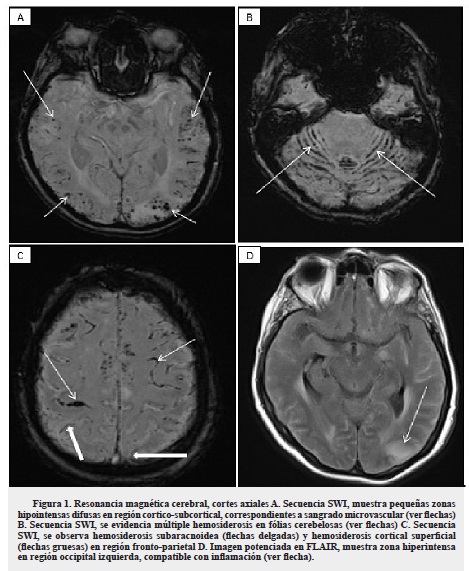

Se realizó electroencefalograma que registró lentificación difusa del trazado por encefalopatía moderada y alteración de la función eléctrica cortical fronto parietal izquierda, sin actividad epileptiforme. La resonancia magnética (RM) de cráneo simple y contrastada mostró múltiples hemorragias puntiformes córtico-subcorticales en hemisferios cerebelosos y región parieto-occipital izquierda con edema vasogénico (figura 1).

Los hallazgos de la AAC en RM de cráneo son inespecíficos, generalmente se observan hiperintensidades cortico-subcorticales en T2 y FLAIR, lesiones lacunares con ausencia de señal en secuencia de gradiente eco, que corresponde a zonas de microsangrados de predominio en las regiones temporal, occipital y cerebelosa. También se han descrito desde hemorragias mayores, hemorragia subaracnoidea (HSA) y edema cerebral focal en relación con la AAC10,20-22, hasta la falta de evidencia de microsangrado en la RM cerebral tal como lo reporta Sakaguchi y colaboradores en su reporte de caso y en la revisión sistemática de la literatura23. La paciente descrita presentaba microsangrados cortico-subcorticales de predominio posterior e infratentorial, hemosiderosis cortical superficial, HSA a nivel de surcos y edema vasogénico local asimétrico, tal como lo mencionan Chung y colaboradores en una propuesta unificada de criterios diagnósticos para AAC-IR, en la categoría posible, sin ayuda histopatológica17.